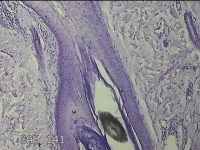

后颈部皮肤结节

性别

男

年龄

45岁

临床诊断

皮肤结节病

一般病史

发现后颈部皮肤结节半年余。

标本名称

大体所见

灰白粉红色组织1.7x0.9x0.3cm一块,表面带梭形皮肤1.7x0.9cm,皮下见结节1.5x1.1cm一个,切开结节呈实性,切面灰白粉红色,质软。

图1